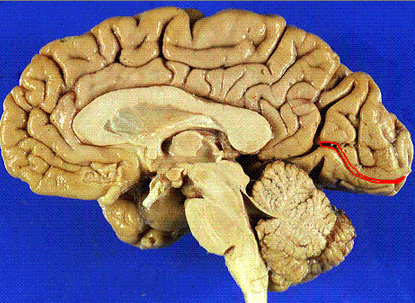

calcarine sulcus

light yellow

primary visual cortex

Pink area

Primary Visual cortex (V1, area 17)

optic tract

visual radiation

prectum

superior colliculis

occulomotor

occulomotor nerve

lateral geniculate n.